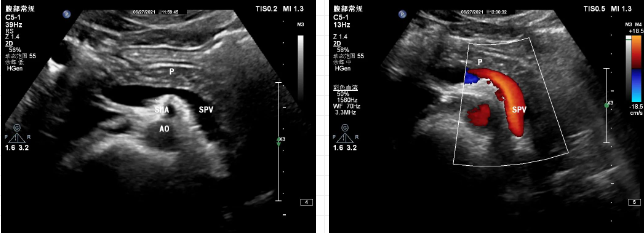

彩超并不是彩色電視,是在黑白二維超聲的基礎(chǔ)上加上彩色多普勒技術(shù),能夠觀察人體器官中的血流情況,以達(dá)到診斷目的。

紅色的是動(dòng)脈,藍(lán)色的是靜脈嗎?

紅色只是代表朝向探頭的血流,藍(lán)色代表背離探頭的血流,顏色用來表示血流方向,而不是區(qū)分動(dòng)靜脈血流。